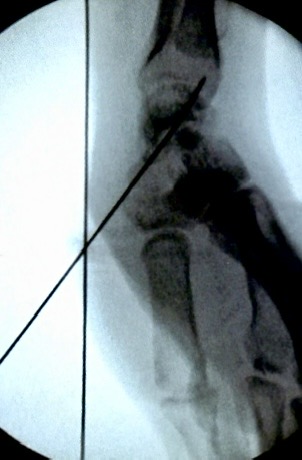

1)臂丛麻醉 ,于体表鼻烟窝处触摸舟骨,并用克氏针标记进针方向,透视后调整。

2)鼻烟窝处做小切口,自远端向近端,向尺骨茎突方向打人导针,

3)透视正侧位,调整导针位置,透视下见导针位置良好后,用空心钻沿着导针钻孔,拧入螺钉,加压包扎伤口或者缝合一针。

拧入空心钉